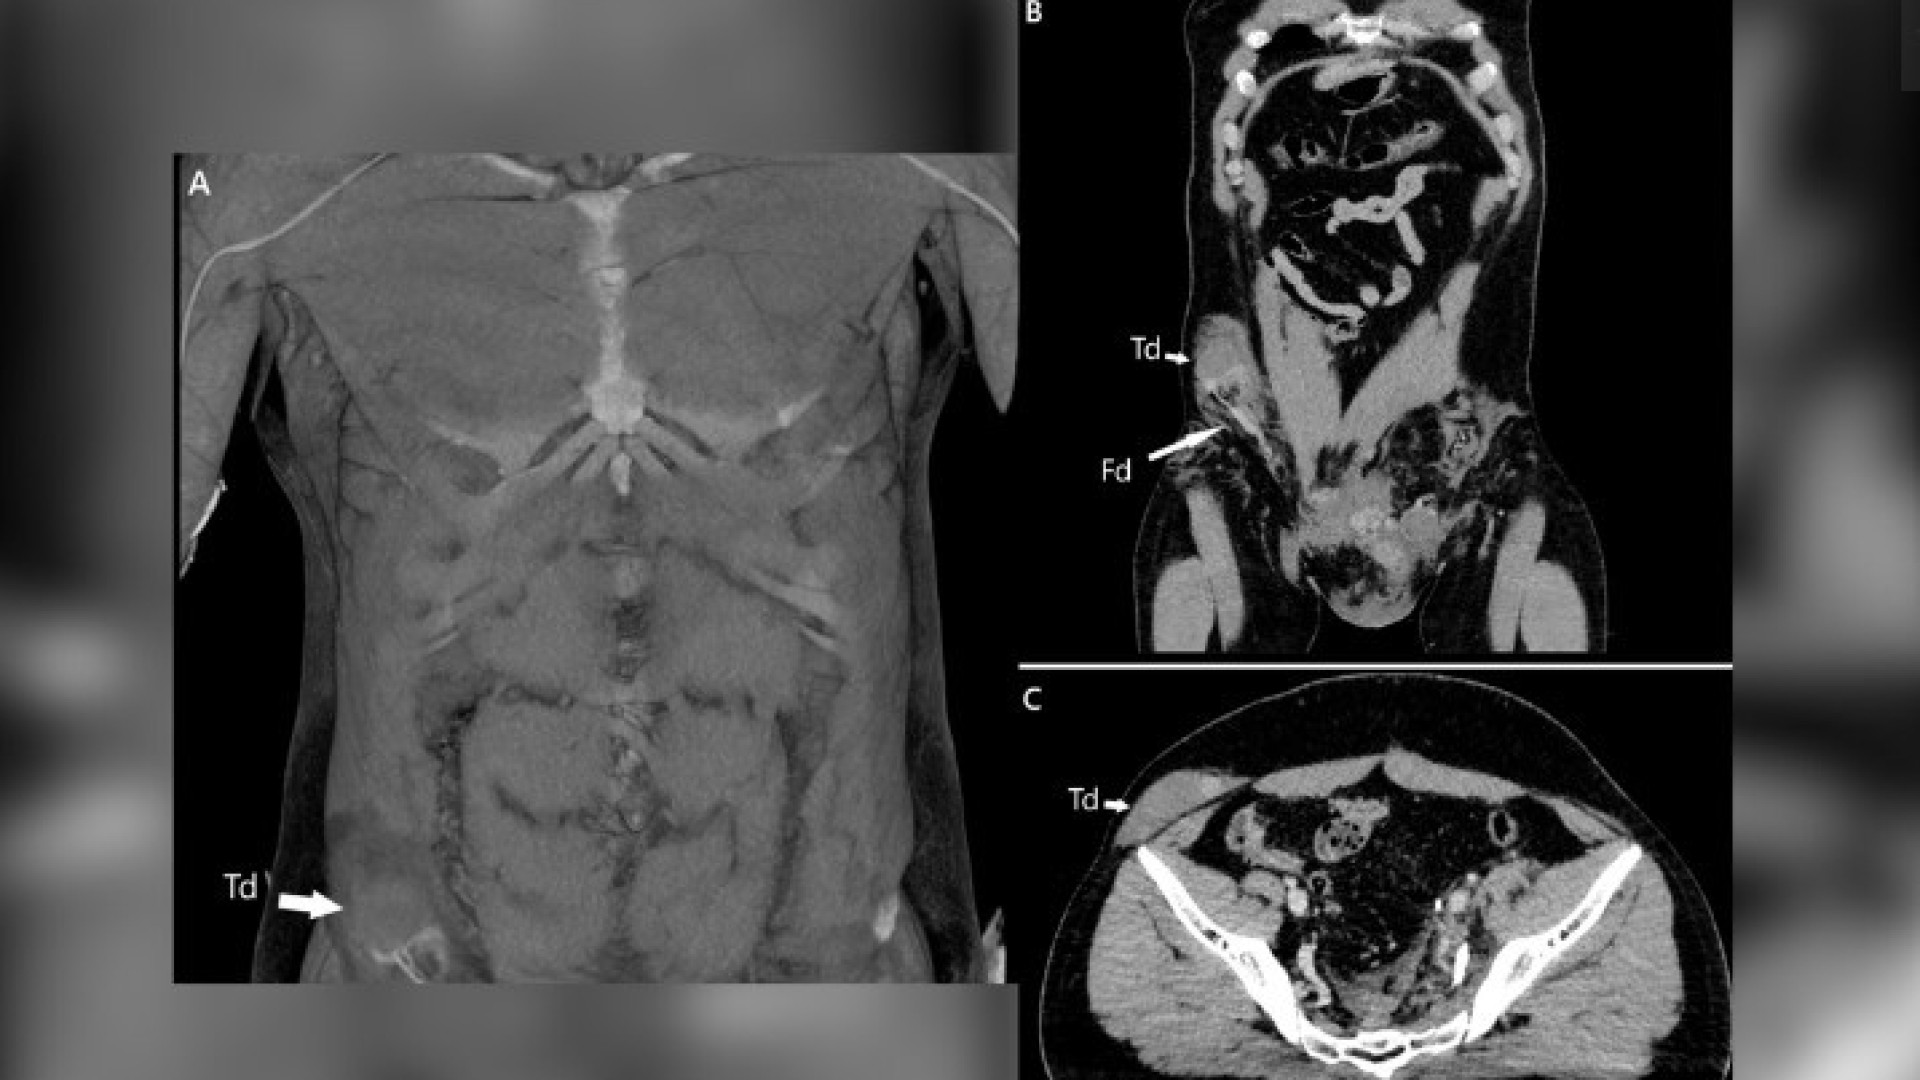

Testículo de homem é deslocado para o abdômen após acidente de moto

Aconteceu devido à força do embate. Se não for detectado a tempo, o incidente pode provocar danos permanentes